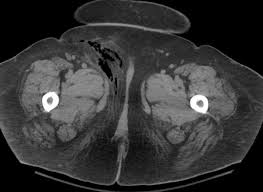

Fournier S Gangrene In The Scrotum Download Scientific Diagram

Fournier S Gangrene In The Scrotum Download Scientific Diagram from www.researchgate.net